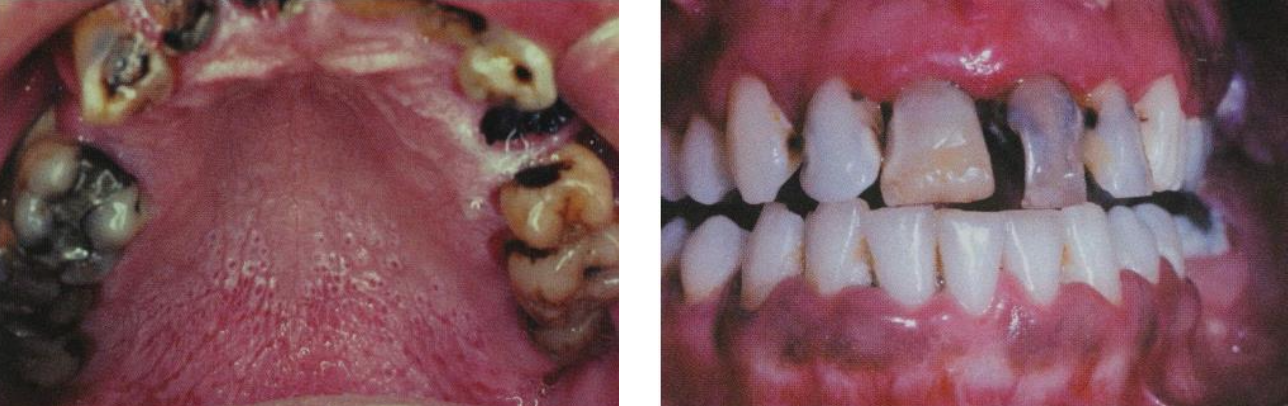

---|---|---|---|---|---|

Dentigerous cyst (DC) | follicle 分離 | 38,48 | 10 - 30y |

Eruption cyst (EC) | Dentigerous 萌發 | 12a, 12b, 34a, ?6 | 10y ↓ | 藍色或紫棕色 ![]() ![]() |

Odontogenic Keratocyst cyst (OKC) |

下顎骨後端,下齒槽管上方 | 10-40y | 組生齒(40%) | |

Radiolucent、 MD方向下顎骨吸收,但牙根完整。 ![]() |

4-8 層、副角化(有核)、Basal cell 為 palisaded(柵狀) | |||||

高復發 (30%) | |||||

Orthokeratinized Odontogenic cyst (OOC) |

- | 下顎後牙 | 年輕人 | 阻生齒 (66%)、 granule layer 明顯 、 生長慢 |